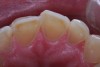

(1.) Toothpaste abuse, biting on hard objects repeatedly, smoking a pipe, or steady use of a hard-bristled toothbrush can lead to excessive abrasive wear.

Figure 1

(2.) Toothpaste abuse, biting on hard objects repeatedly, smoking a pipe, or steady use of a hard-bristled toothbrush can lead to excessive abrasive wear.

Figure 2